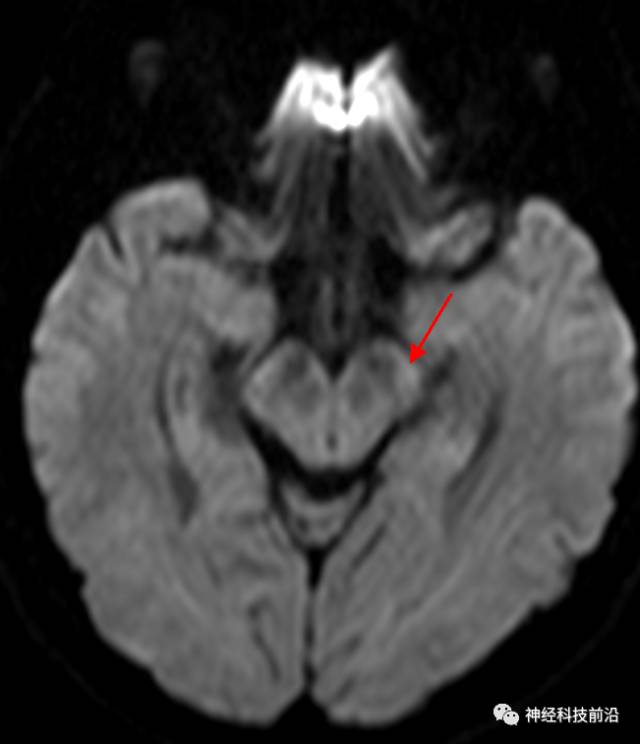

DWI脑干和内囊后肢经常显示为高信号,它是什么纤维束呢?皮质脊髓束?

皮质脑桥束与脑干高信号(黄色)纤维束

脑干内高信号为一近环形纤维束,其作用尚待研究。

终上所述:脑干高信号为一近环形纤维束,内囊后肢高信号为皮质脑桥束,皮质脊髓束在中脑位置略靠后。高信号位于中脑前缘,是皮质脑桥束的位置所在,另外有部分桥连纤维。